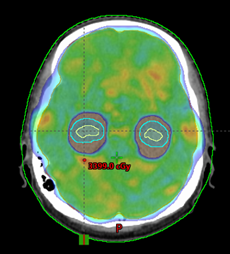

Eclipse v.15 es el sistema de planeación de tratamiento más moderno del que dispone Varian Medical Systems. Este le permite a los radioncólogos, dosimetristas y físicos médicos, a través de múltiples aplicaciones informáticas y algoritmos, realizar la planeación de los tratamientos de radioterapia en un entorno totalmente digital y tridimensional para visualizar la dosis que recibirán los volúmenes de tratamiento y, al mismo tiempo, encontrar la configuración óptima minimizando la dosis en los tejidos sanos.